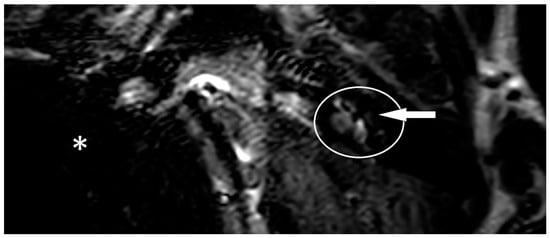

One year after the CI, the patient suffered from new attacks of rotational vertigo. There was no change in the vestibular examinations. An MRI with an ELH sequence was performed, and a cochlear ELH grade 1 was also observed on the left side (Figure 1). Since that time, the patient has had no further attacks and is stable, so no escalation of therapy was necessary.

Figure 1. MRI of patient one in a three-dimensional fluid-attenuated inversion recovery (3D-FLAIR) sequence with delayed contrast. The left inner ear is marked with a white circle. The implanted side cannot be seen because of an artifact of the implant. The artifact is marked with a white star. It is possible to mark out a cochlear hydrops grade 1, which is marked with a white arrow.